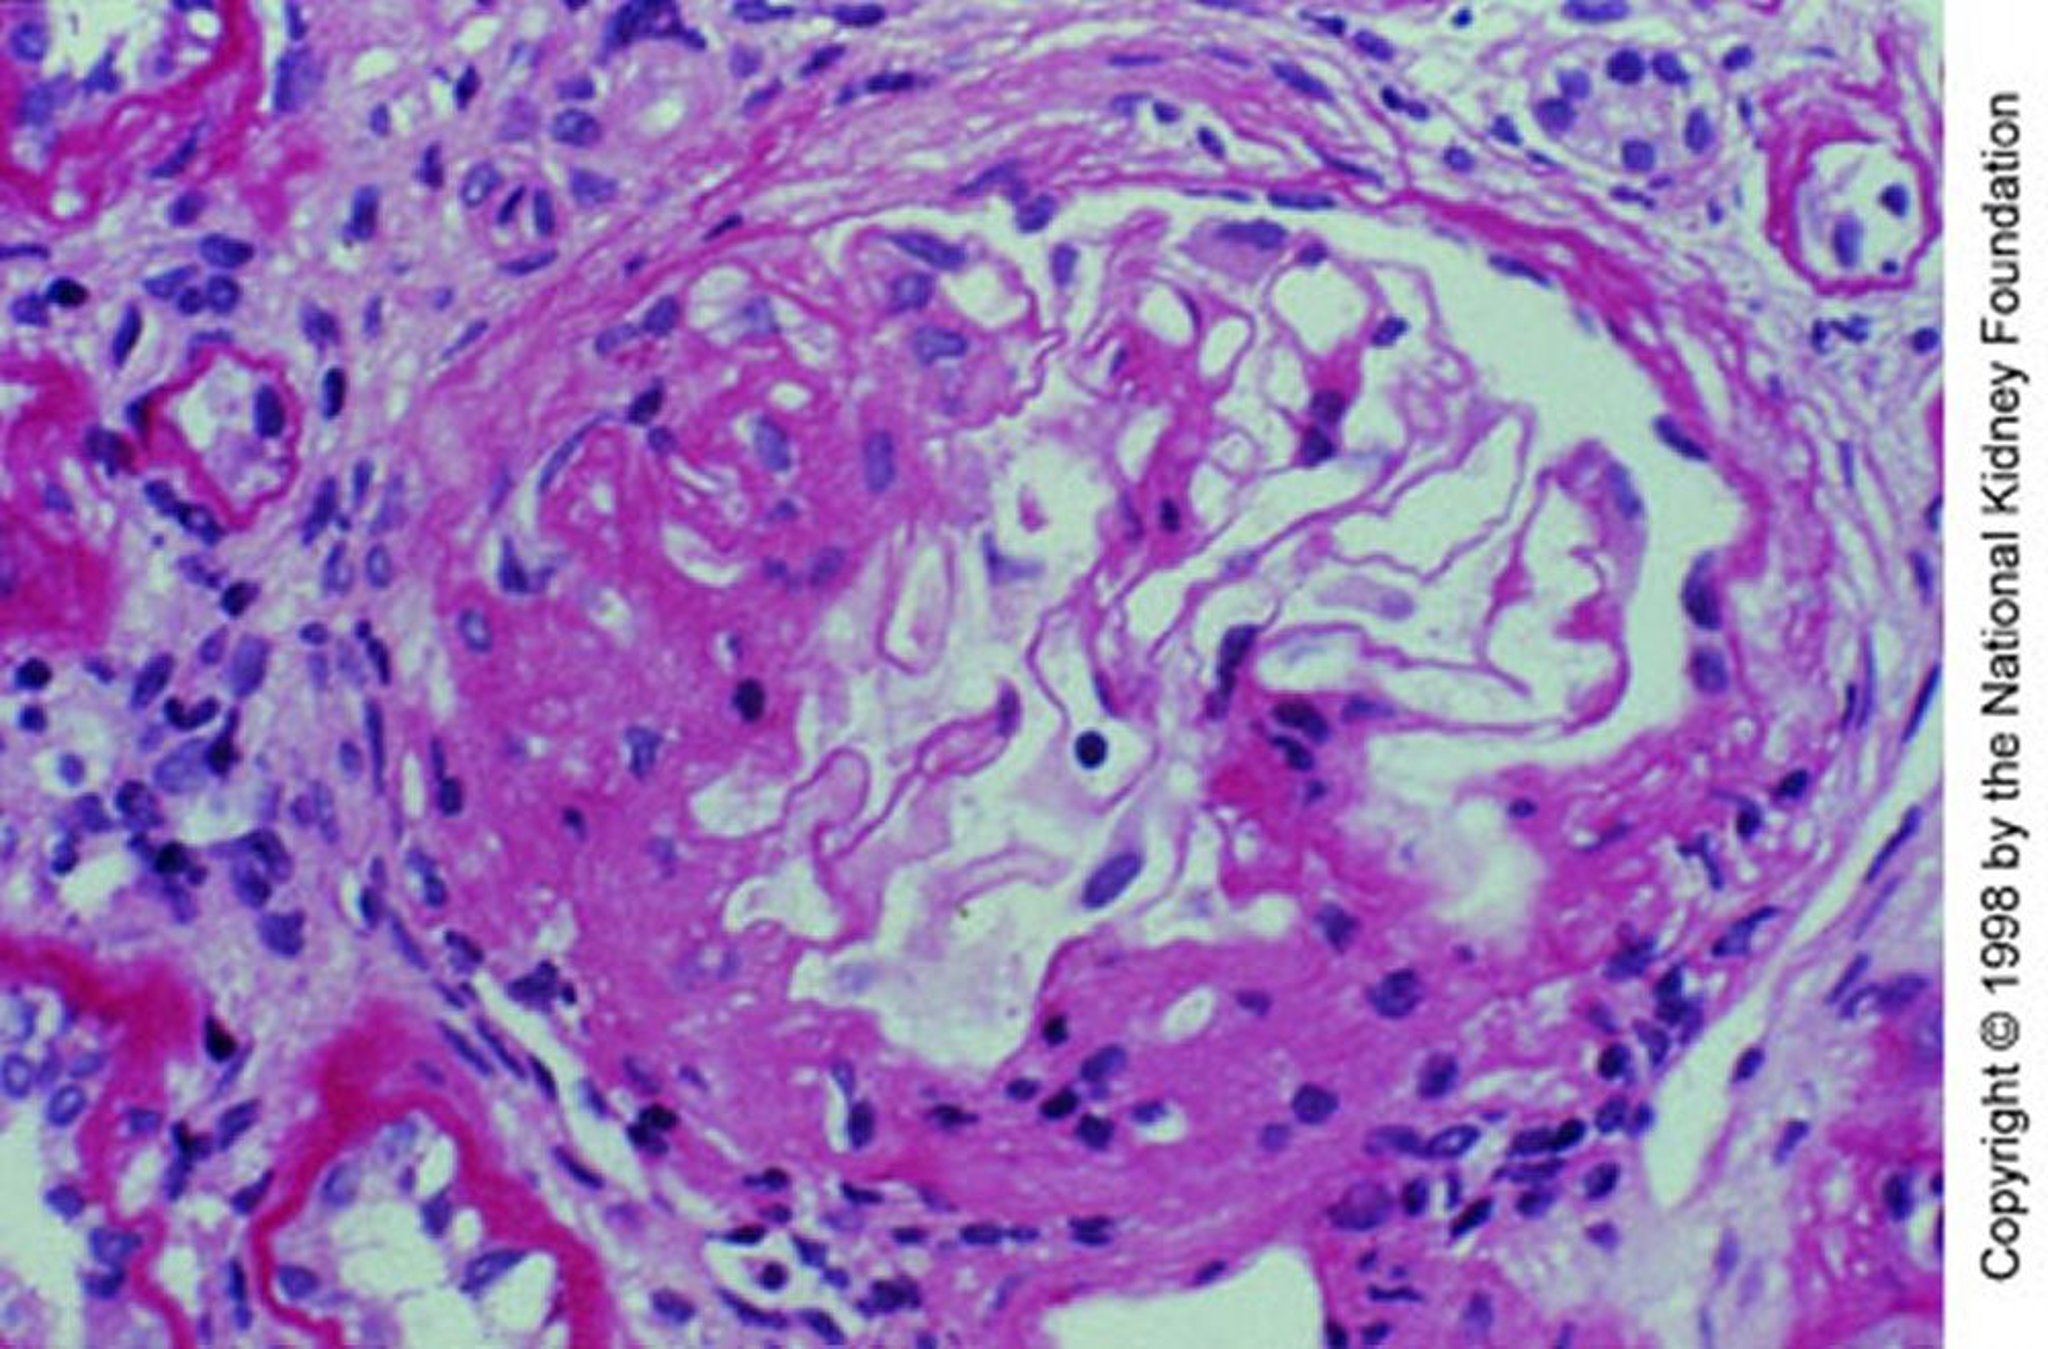

IgA腎症(メサンギウム領域の拡大)

分節性硬化を伴うメサンギウム領域の拡大(PAS染色,200倍)。

Image provided by Agnes Fogo, MD, and the American Journal of Kidney Diseases' Atlas of Renal Pathology (see www.ajkd.org).